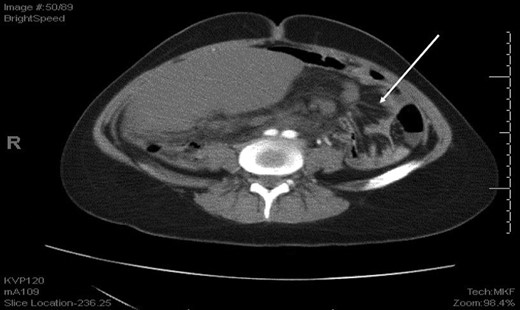

Laboratory investigation showed a white blood cell count of 15.13 × 103/UL, (mainly neutrophilia of 90.3%), a hemoglobin level of 9.4 g/dL, and a platelet count of 189 × 103/UL. The other biochemical parameters including liver enzymes were normal apart from a trace of jaundice, with total Bilirubin of 2.43 mg/dL and direct Bilirubin of 0.45 mg/dL. Chest X-ray showed bowel loops at the splenic fossa (Fig. 1). An initial diagnosis of a torted ovarian cyst was made. A pelvi-abdominal ultrasound revealed normal adnexa but a right-sided soft pelvic-abdominal mass with the absence of a splenic shadow at the left hypochondrium. Subsequently, CT scan of the abdomen and pelvis revealed a large right-sided infarcted spleen of 30 × 16 × 10 cm3 (Fig. 2) and a ‘whirl sign’ of the splenic pedicle (Fig. 3). Furthermore, CT scan showed signs of portal hypertension (Fig. 4) associated with mesenteric varices (Fig. 5). The patient subsequently underwent a surgical exploration.

An axial CT shows dilated engorged mesenteric vessels (white arrow) indicating mesenteric varices.